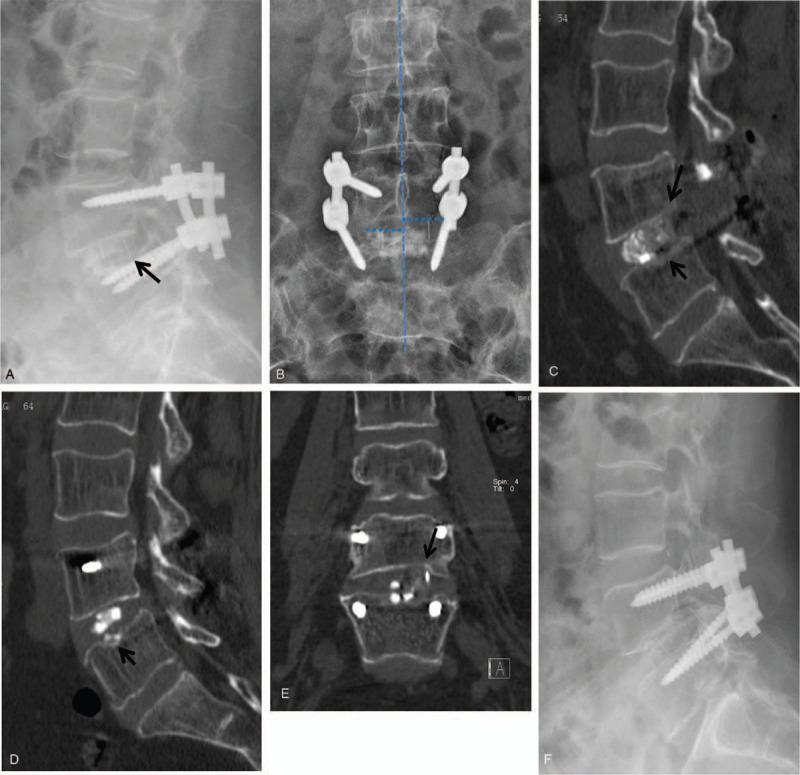

Although transforaminal lumbar interbody fusion (TLIF) is a widely accepted procedure, major complications such as cage retropulsion (CR) can cause poor clinical outcomes. Endplate injury (EI) was recently identified as a risk factor for CR, present in most levels developing CR. However, most EIs occurred in non-CR levels, and the features of EIs in CR levels remain unknown.The aim of this study was to identify risk factors for CR following TLIF; in particular, to investigate the relationship between EIs and CR, and to explore the features of EIs in CR.Between October 2010 and December 2016, 1052 patients with various degenerative lumbar spinal diseases underwent bilateral instrumented TLIF. Their medical records, radiological factors, and surgical factors were reviewed and factors affecting the incidence of CR were analyzed.Twenty-one patients developed CR. Nine had back pain or leg pain, of which six required revision surgery. A pear-shaped disc, posterior cage positioning and EI were significantly correlated with CR (P < .001, P = .001, and P < .001, respectively). Computed tomography (CT) scans revealed the characteristics of EIs in levels with and without CR. The majority of CR levels with EIs exhibited apparent compression damage in the posterior part of cranial endplate on the decompressed side (17/18), accompanied by caudal EIs isolated in the central portion. However, in the control group, the cranial EIs involving the posterior part was only found in four of the total 148 levels (P < .001). Most of the injuries were confined to the central portion of the cranial or caudal endplate or both endplates (35 in 148 levels, 23.6%). Additionally, beyond cage breaching into the cortical endplate on lateral radiographs, a characteristic appearance of coronal cage misalignment was found on AP radiographs in CR levels with EIs.A pear-shaped disc, posterior cage positioning and EI were identified as risk factors for CR. EI involving the posterior epiphyseal rim had influence on the development of CR. Targeted protection of the posterior margin of adjacent endplates, careful evaluation of intraoperative radiographs, and timely remedial measures may help to reduce the risks of CR.

尽管经椎间孔腰椎体间融合术(TLIF)是一种广泛接受的手术方法,但严重并发症如 cage retropulsion(CR)会导致不良的临床结果。最近发现终板损伤(EI)是 CR 的危险因素,大多数发生 CR 的节段都存在 EI。然而,大多数 EI 发生在非 CR 节段,CR 节段的 EI 特征尚不清楚。本研究旨在确定 TLIF 后发生 CR 的危险因素;特别是,研究 EI 与 CR 的关系,并探讨 CR 中 EI 的特征。2010 年 10 月至 2016 年 12 月,1052 例各种退行性腰椎疾病患者接受双侧器械 TLIF。回顾其病历、影像学因素和手术因素,并分析影响 CR 发生率的因素。21 例患者发生 CR。9 例有腰痛或腿痛,其中 6 例需要翻修手术。梨形椎间盘、后方 cage 定位和 EI 与 CR 显著相关(P<0.001,P=0.001,P<0.001)。CT 扫描显示了有和无 EI 的 CR 节段的特点。大多数有 EI 的 CR 节段在减压侧颅侧终板后部表现出明显的压缩损伤(17/18),伴有中央部孤立的尾侧 EI。然而,在对照组中,总共 148 个节段中只有 4 个发现颅侧 EI 累及后部(P<0.001)。大多数损伤仅限于颅侧或尾侧终板的中央部分或两个终板(148 个节段中有 35 个,23.6%)。此外,除了侧位片上 cage 突破皮质终板外,还发现 CR 节段有 EI 的正位片上冠状 cage 错位的特征性表现。梨形椎间盘、后方 cage 定位和 EI 是 CR 的危险因素。累及骺环后部的 EI 对 CR 的发展有影响。有针对性地保护相邻终板的后部边缘,仔细评估术中 X 线片,并及时采取补救措施,可能有助于降低 CR 的风险。